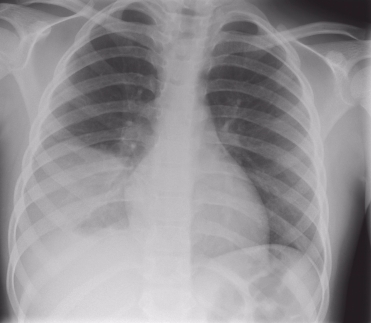

ДИАГНОСТИКА

Диагноз устанавливается после осмотра больного, лабораторных и инструментальных исследований. Проводятся: клинический анализ крови, рентгенография грудной клетки, КТ грудной клетки, по показаниям бронхоскопия, исследование мокроты (микроскопия и бактериологическое исследование), исследование крови на стерильность (гемокультура), пульсоксиметрия (количество кислорода в крови)